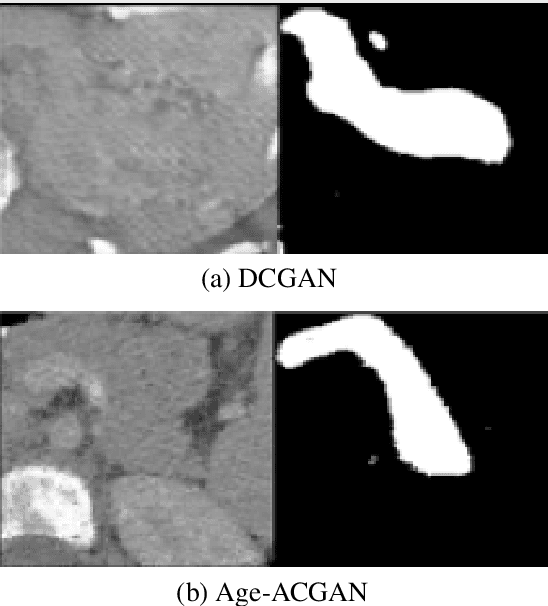

Abstract:Deep learning is a popular and powerful tool in computed tomography (CT) image processing such as organ segmentation, but its requirement of large training datasets remains a challenge. Even though there is a large anatomical variability for children during their growth, the training datasets for pediatric CT scans are especially hard to obtain due to risks of radiation to children. In this paper, we propose a method to conditionally synthesize realistic pediatric CT images using a new auxiliary classifier generative adversarial network (ACGAN) architecture by taking age information into account. The proposed network generated age-conditioned high-resolution CT images to enrich pediatric training datasets.